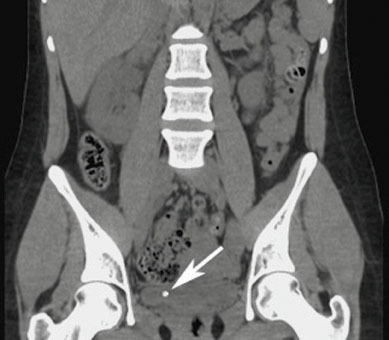

Vladimir Gomola, Jacques Hubert (La Revue du Praticien) Tomodensitométrie non injectée en coupe frontale montrant une lithiase du bas uretère droit au niveau de la jonction vésico-urétérale.